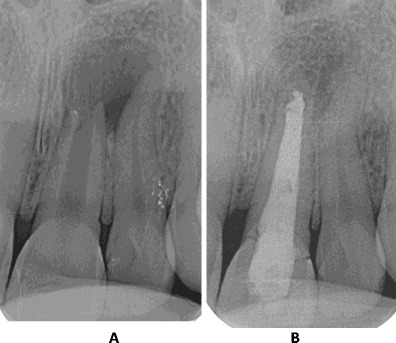

PAINLESS ROOT CANAL TREATMENTS

ADVANCED SINGLE VISIT ROOT CANAL TREATMENTS

Indicated when the tooth pulp is infected due to deep decay, trauma, or cracks.

Benefits include:

Modern techniques ensure safe, comfortable, and successful treatment.

Based on clinical condition:

For teeth with extensive damage, we reinforce structure before crown placement, ensuring strength and longevity.